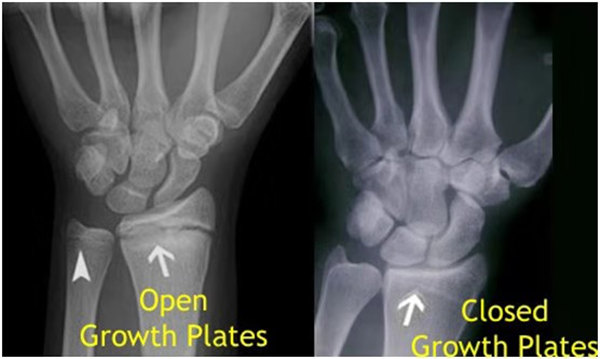

其實想要了解孩子的生長發(fā)育情況或者說孩子未來身高的趨勢,測骨齡是個好辦法。臨床上通常拍攝兒童的左手正位X光片 , 采用《中華-05》骨齡標準對手腕骨發(fā)育程度進行骨齡評價。

我們都知道,人體的高矮是由骨骼的生長發(fā)育決定的,特別是下肢長骨。長骨呈長管狀,在長骨的兩端有一種專管骨骼生長的骺軟骨,它與干骺端之間有一盤狀軟骨結構稱為骺板(線),在幼兒的X光片上表現(xiàn)為一條較寬的透光帶。 (見下圖)

未成年時隨著年齡的增加骺軟骨端不斷骨化,骨骼就不斷增長。當骨骺線完全閉合時骨骼就停止生長,個子也就不再增長了。一般骨骺端完全閉合的年齡是18~20歲左右。